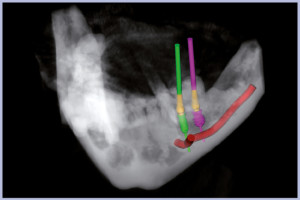

Per riabilitare la masticazione del terzo quadrante, con osso gravemente atrofico, si procede allo studio del caso con esame radiologico 3D e posizionamento virtuale di impianti Exacone® Leone. La prima valutazione è stata eseguita con il software dell’apparecchio radiografico Cone Beam presente in studio. Dopo aver verificato che la quantità di osso residuo fosse sufficiente all’inserimento di due impianti, seppur di dimensioni ridotte, in sede 3.5 e 3.6 senza l’ausilio di tecniche di rigenerazione ossea (Figg. 1-3), si richiede al laboratorio di confezionare una mascherina radiologica con ceratura diagnostica radiopaca e repere standardizzato a livello incisale come da protocollo Leone (Figg. 4, 5). Si verifica quindi clinicamente l’assenza di mobilità della mascherina dopo il posizionamento nel cavo orale del paziente (Figg. 6, 7). Si effettua una CBCT con la mascherina in posizione e l’esame viene inviato in formato DICOM all’azienda Leone assieme al modello master della paziente. L’azienda provvede quindi ad inviare agli Autori il software 3Diagnosys (software di progettazione) in licenza monopaziente con caricati i file DICOM ricevuti; il software viene quindi utilizzato per la progettazione definitiva del caso (Figg. 8-12).

Una volta definito il progetto, gli Autori lo hanno inviato all’azienda Leone che ha confezionato mediante stereolitografia il modello Master 3D, copia esatta del master in gesso sul quale è stata costruita la mascherina radiologica, con gli analoghi degli impianti posizionati secondo il progetto virtuale (Figg. 13 a-d).

Viene quindi richiesto al tecnico di modificare in laboratorio la mascherina radiologica mediante il posizionamento delle boccole di guida adatte agli impianti da posizionare (Exacone® 6.5 e Exacone® 3,3×8) in asse con gli analoghi del modello Master 3D ed eliminando il repere radiologico standardizzato, trasformandola così nella dima chirurgica (Figg. 14, 15). Si procede quindi alla prova della mascherina sulla paziente per verificarne la stabilità e la corrispondenza esatta con il modello Master 3D (Fig. 16). La seduta chirurgica con tecnica flapless, guida chirurgica e Frese Zero1 dedicate non presenta alcuna difficoltà ; al termine dell’inserimento si posizionano sugli impianti tappi di guarigione bassi per permettere loro di guarire con tecnica sommersa (Figg. 17-27). Si effettua nella stessa seduta una CBCT che dimostra che la posizione clinica degli impianti risulta sovrapponibile a quella progettata dagli Autori (Figg. 28-30).

- Figg. 8-12 – Pianificazione implantare con software 3Diagnosys Leone

- Fig. 9

- Fig. 10

- Fig. 11

- Fig. 12